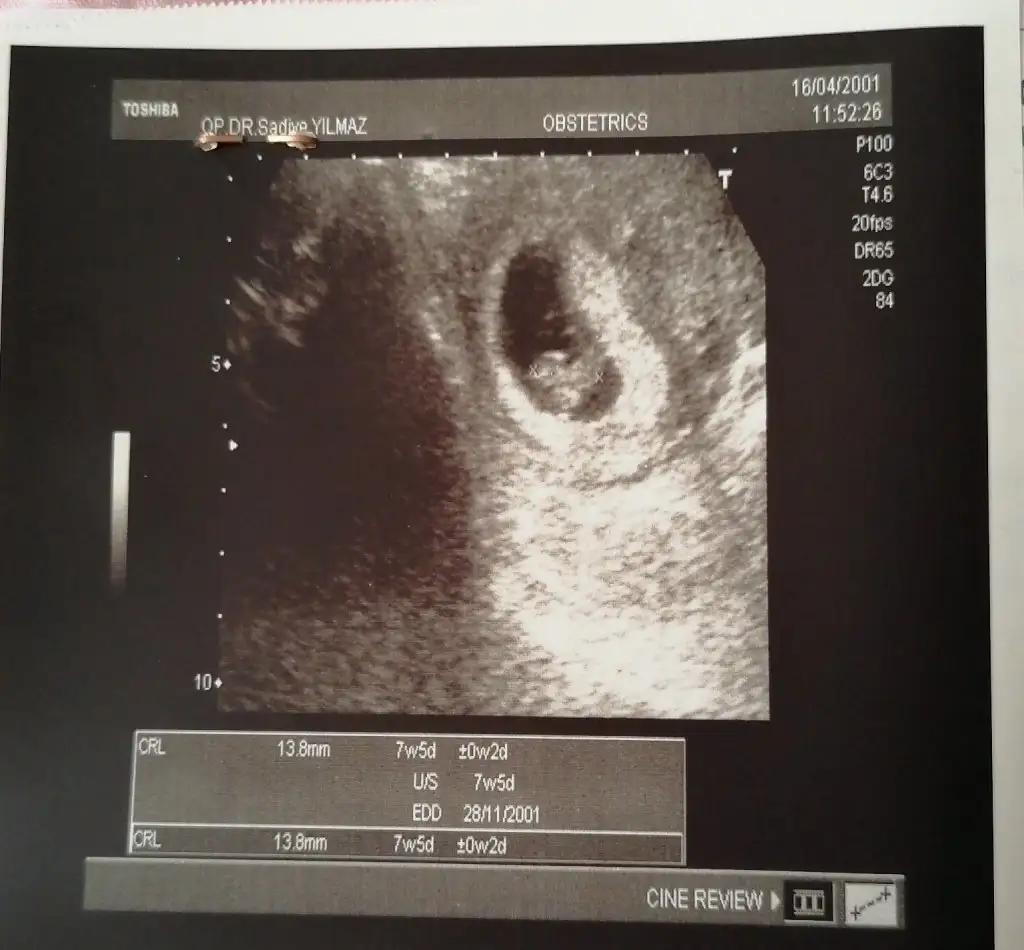

Ay bir de cihazın tarihi yanlışmış, bana diyor ki Aralık sonu ocak başı doğum var. Şoka girdim sonradan anladı, o da gülmeye başladı düzeltti tarihiEki Görüntüle 2893686 kızlar selam benim bebik de büyümüşçok duygusal bi durum bu yaaa önceki ultrason ile arada fark görmek. Rabbim her isteyene hayırlısıyla tattırsın bu duyguyu. 7+3 dedi uygulamalara göre 7+5 bi fark olduğunu sanmıyorum. Yürüyüş sonrası karın ağrısı durumunu anlattım progestan başlayalım önlem olsun dedi. Bu arada bizde kan uyuşmazlığı var, başka olan var mı acaba??

Aa ne güzel haftası yaziyo ultrasonda benimkinde yazmıyor ya da ben mi anlamıyorumEki Görüntüle 2893686 kızlar selam benim bebik de büyümüşçok duygusal bi durum bu yaaa önceki ultrason ile arada fark görmek. Rabbim her isteyene hayırlısıyla tattırsın bu duyguyu. 7+3 dedi uygulamalara göre 7+5 bi fark olduğunu sanmıyorum. Yürüyüş sonrası karın ağrısı durumunu anlattım progestan başlayalım önlem olsun dedi. Bu arada bizde kan uyuşmazlığı var, başka olan var mı acaba??